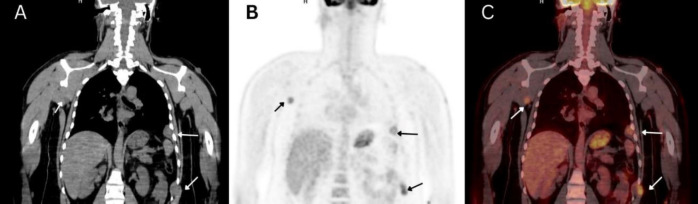

恶性周围神经鞘瘤(MPNST)是一种罕见的侵袭性软组织肉瘤,源于周围神经,往往给诊断和治疗带来挑战。恶性神经鞘瘤(MPNST)可能偶发,也可能与 1 型神经纤维瘤病(NF1)伴发,NF1 是一种由 NF1 基因突变引起的遗传性疾病。本报告介绍了一例独特的病例,患者是一名 33 岁男性,患有进行性干咳、声音嘶哑和颈部肿胀,接受了甲状腺全切除术,发现甲状腺内有一个高级别恶性周围神经鞘瘤。经 FDG PET/CT 检查,最终确诊为 NF1。由于在甲状腺内发现 MPNST 并同时发现 NF1 的罕见性,该病例显得尤为突出。它强调了对MPNST患者进行NF1筛查的重要性,反之亦然,突出了FDG PET/CT在综合评估中不断扩大的作用。据我们所知,本报告是全球首例NF1相关的甲状腺受累的MPNST病例。

Malignant peripheral nerve sheath tumors (MPNST) are rare, aggressive soft tissue sarcomas that arise from peripheral nerves and often present a diagnostic and therapeutic challenge. They can occur sporadically or in association with neurofibromatosis type 1 (NF1), a genetic disorder caused by mutations in the NF1 gene. This report presents the unique case of a 33-year-old male with progressive dry cough, hoarseness, and neck swelling who underwent a total thyroidectomy, revealing a high-grade malignant peripheral nerve sheath tumor invading the thyroid. FDG PET/CT led to the additional diagnosis of NF1. This case stands out due to the rarity of finding an MPNST within the thyroid and the simultaneous identification of NF1. It underscores the importance of screening MPNST patients for NF1 and vice versa, spotlighting the expanding role of FDG PET/CT in comprehensive evaluations. To our knowledge, this report presents the first case of NF1-associated MPNST with thyroid involvement worldwide.